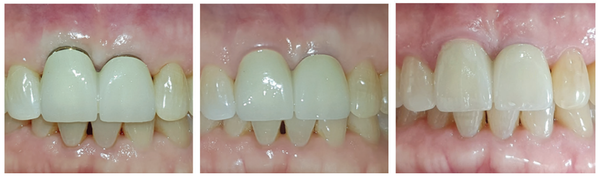

Magic Cuff의 다른 특장점 중 하나는 임플란트 식립 후 임플란트 주변으로 치유된 연조직의 sealing에 손상을 주지 않아 술 후 장시간이 지난 후에도 심미적인 연조직 상태를 기대할 수 있다는 것이다.

일반적으로 bone level 2-piece 임플란트를 식립한 후에 인상 채득과 crown setting 과정에서 임플란트 주변의 연조직 sealing이 손상될 수 있으나 MagiCore는 연조직 점착이 용이한 표면처리와 디자인이 적용된 Magic Cuff를 활용해 건강한 연조직 상태를 유지할 수 있다.

이에 반해 MagiCore 임플란트는 일체형 구조를 가진 tissue over level의 임플란트로 그 구조상 microgap과 micromobility가 존재할 수 없으며 인상 채득 과정이나 crownsetting 과정에서도 결합조직과 MagicCuff 사이의 sealing이 손상되지 않는다. (그림 5)

따라서 (그림 2-2)와 같이 잇몸 모양을 수정해서 식립해도 처음 형성된 연조직 sealing이 단단하고 견고한 결합을 유지할 수 있다. 또한, 이 과정에서 flap 형성 없이 수술이 이뤄지므로 gingiva의 연속성이 유지돼 보다 빠른 치유와 연조직 remodeling을 기대할 수 있다.

Magic Cuff는 2~5 mm의 다양한 길이가 있으므로 이를 잘 활용한다면 치조골 상방의 골흡수가 심하고 상대적으로 gingiva가 두꺼워진 경우에도 알맞게 적용할 수 있다. 특히 협측의 여유 공간을 충분히 두고 protocol에 따른 식립이 이루어진다면 시간이 흐를수록 gingiva line이 상방으로 자라 올라오는 on-growth 현상도 기대할 수 있다. (그림 6, 7)